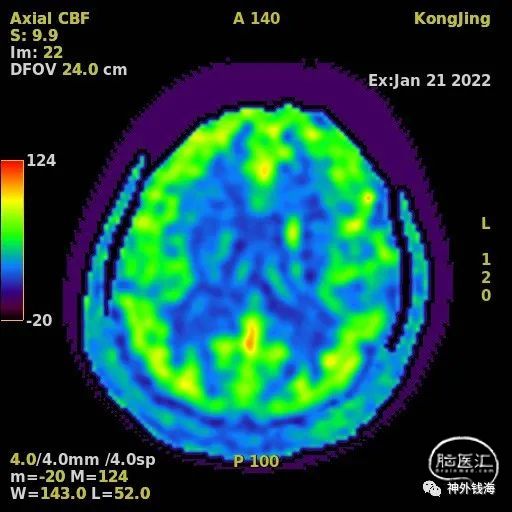

图3 头部磁共振ASL序列可见左额叶脑血流关注下降。说明左侧半球有缺血表现。